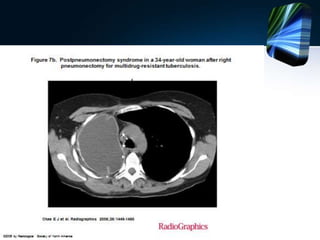

SD. Postneumonectomia